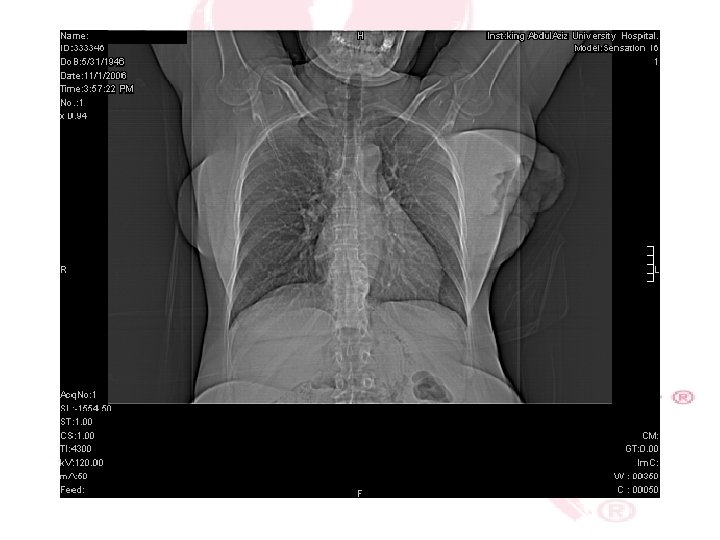

CHEST X-RAY